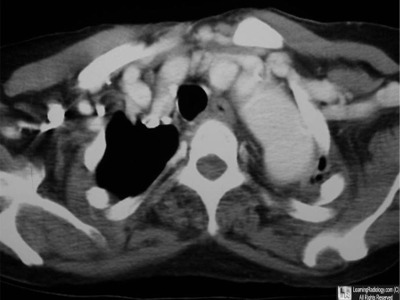

Contrast-enhanced Axial CT of Upper Chest

5. Cervical Aortic Arch

Cervical Aortic Arch

• Rare congenital anomaly

• Usually defined as a supraclavicular position of the aortic arch

• More common on the right side

• 2:1 female:male predominance

47 year-old with pulsatile left supraclavicular mass